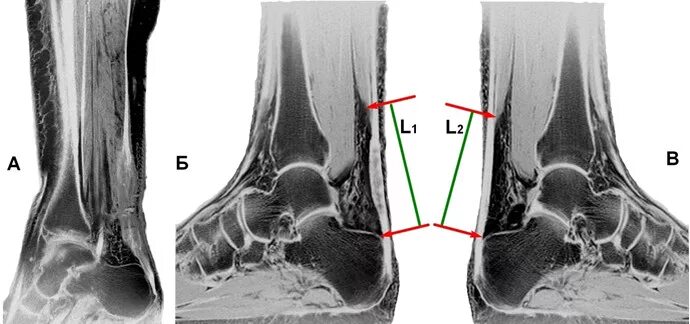

Мрт ахиллового сухожилия